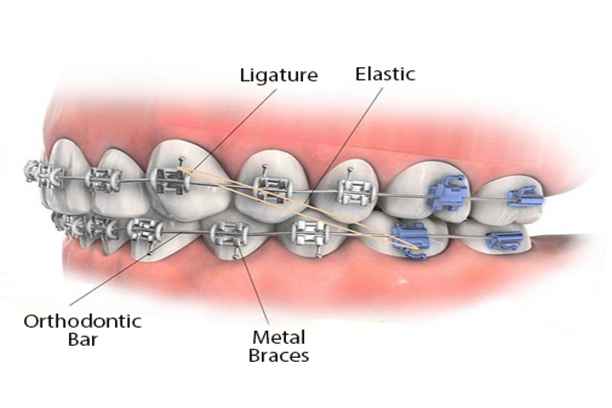

مكونات تقويم الأسنان

يتكون التقويم من عدة عناصر متكاملة تعمل معًا لتحريك الأسنان تدريجيًا:

- الحاصرات أو الأقواس المعدنية أو الخزفية التي تثبت على سطح الأسنان

- الأسلاك القوسية التي توصل القوى بين الحاصرات لتوجيه حركة الأسنان

- الأشرطة المطاطية أو الروابط الصغيرة التي تساعد في تثبيت الضغط والتحكم في الإطباق

- بعض أنواع التقويم الداخلي أو الشفاف تحتوي على قوالب خاصة لتحديد حركة الأسنان بدقة

- الأدوات المساعدة مثل الشمع الطبي وفرشاة التقويم وخيط الأسنان الخاص

مع فهم مكونات تقويم الأسنان يصبح من الأسهل للمريض الالتزام بالعناية اليومية، والتأكد من أن كل عنصر يؤدي وظيفته بالشكل الصحيح، ما يعزز سرعة النتائج وفعاليتها.